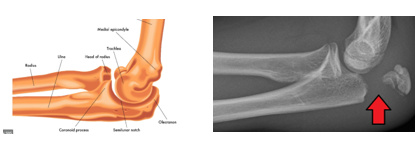

Giải phẫu

Mỏm khuỷu nằm sát ngay dưới da, nên dễ bị tổn thương khi té ngã

Sau đó bác sĩ sẽ cho chụp Xquang ở khuỷu tay, trên phim sẽ nhìn thấy đường gãy, có nát xương nhiều không, và có phân loại phù hợp